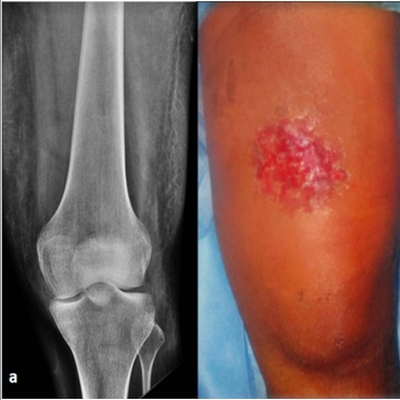

Click on an image below to view more info.